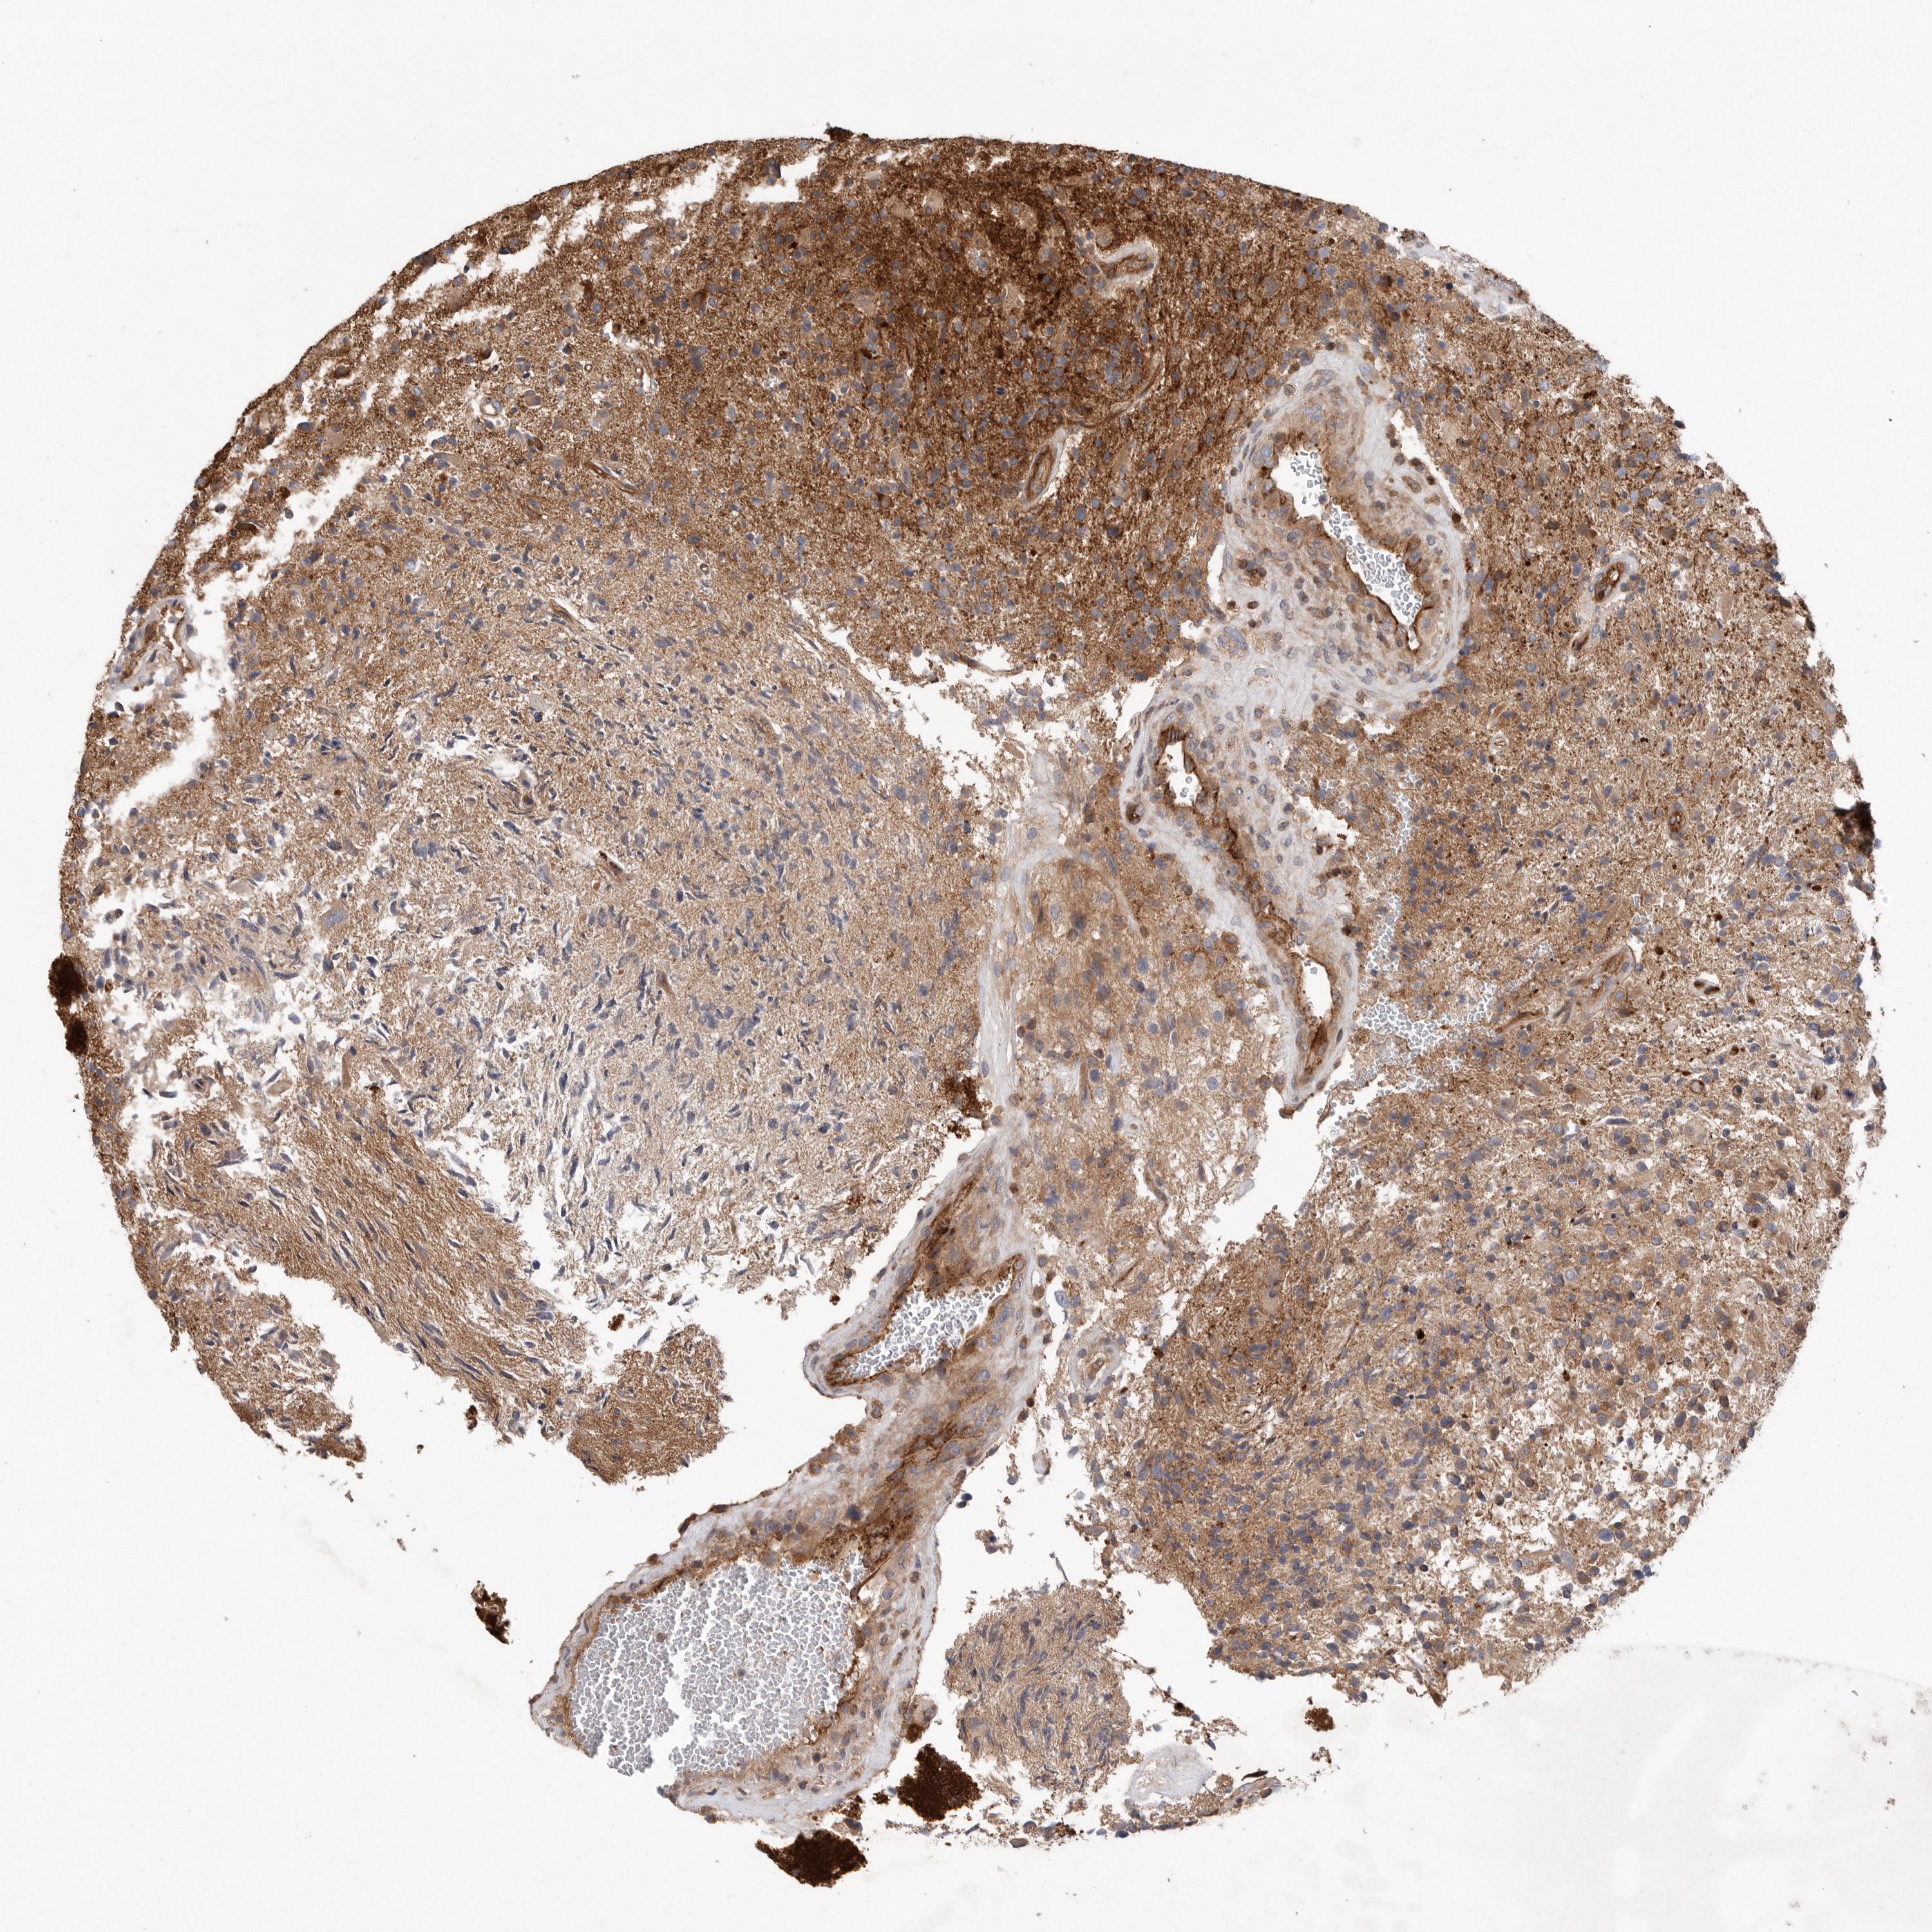

GLIOMA - Protein expressioni

A mouse-over function shows sample information and annotation data. Click on an image to view it in a full screen mode. Samples can be filtered based on level of antibody staining by selecting one or several of the following categories: high, medium, low and not detected. The assay and annotation is described here.

Note that samples used for immunohistochemistry by the Human Protein Atlas do not correspond to samples in the TCGA dataset.

Antibody stainingi

Antibody staining in the annotated cell types in the current human tissue is reported as not detected, low, medium, or high, based on conventional immunohistochemistry profiling in selected tissues. This score is based on the combination of the staining intensity and fraction of stained cells.

Each image is clickable and will lead to virtual microscopy that enables deeper exploration of all samples and also displays staining intensity scores, fraction scores and subcellular localization as well as patient and tissue information for each sample.

Antibody HPA026294

Antibody HPA053709

Staining

High

Medium

Low

Not detected

Intensity

Strong

Moderate

Weak

Negative

Quantity

>75%

75%-25%

<25%

None

Location

Nuclear

Cytoplasmic/membranous

Cytoplasmic/membranous,nuclear

Glioma, malignant, High grade

Glioma, malignant, Low grade

Glioblastoma, NOS